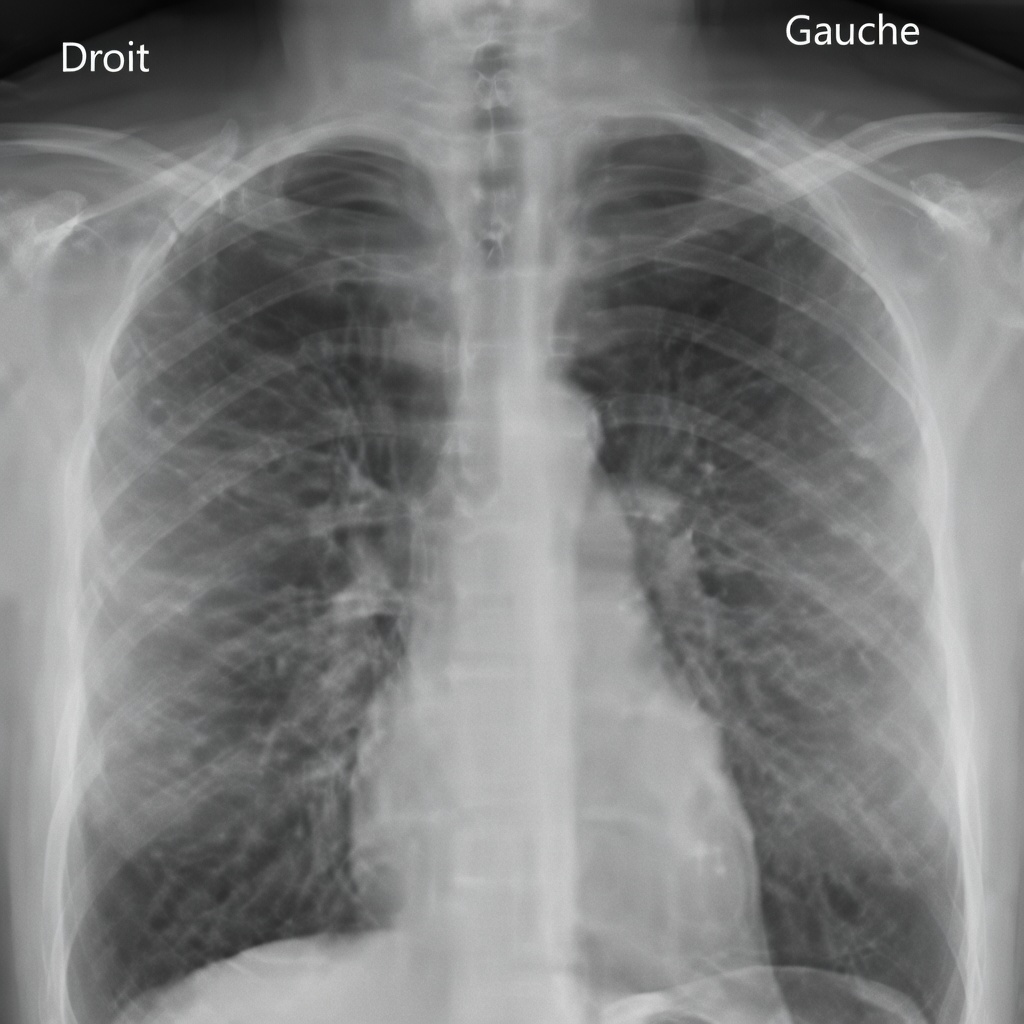

4) Radiographie pulmonaire (radio du thorax) systématique : inutile chez les non-fumeurs sans symptôme

La radiographie du thorax réalisée « par habitude » est un exemple classique d’examen à faible valeur ajoutée chez les non-fumeurs sans problème respiratoire. Même si la dose de radiation est limitée, le risque d’images incidentes et d’explorations inutiles existe.

Les recommandations actuelles privilégient une approche ciblée : une radio thoracique est pertinente lorsqu’il y a des symptômes (toux persistante, fièvre prolongée, essoufflement, douleur thoracique) ou un contexte médical précis, plutôt qu’un contrôle annuel automatique.